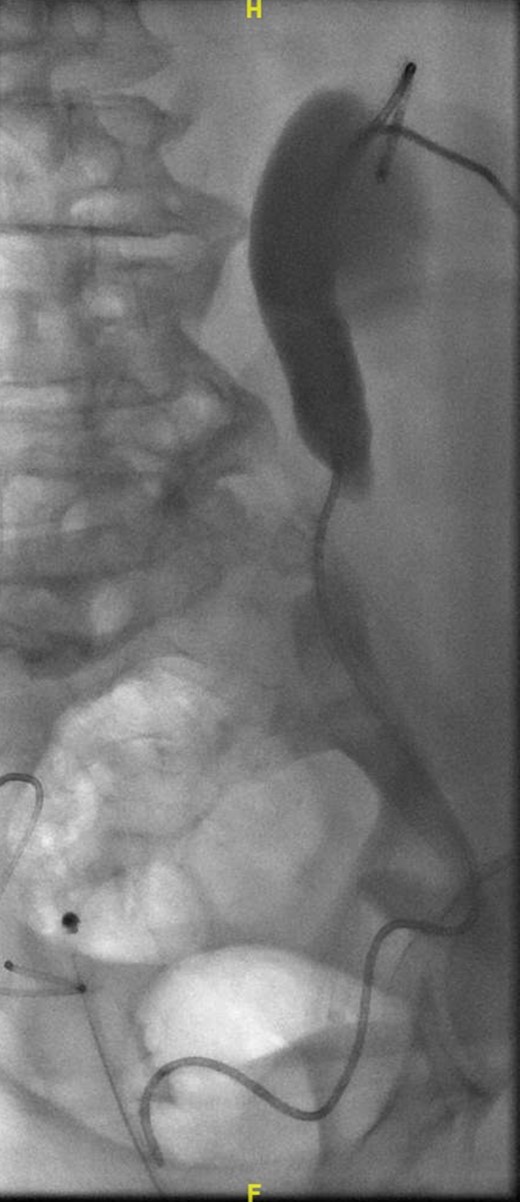

A week later, a left nephrostogram showed a capacious upper urinary tract with a deviated lower ureter which tapered in the pelvis with no filling defects seen above this level (Fig. 5). The appearances were in keeping with extrinsic compression. A week later, rigid cystoscopy, right-sided retrograde study, right JJ stent insertion and cystogram were performed. The left ureteric orifice could not be identified. The cystogram demonstrated no evidence of bladder herniation to the inguinal hernia (Fig. 6). Two months later, a non-contrast CT of the urinary tract demonstrated partial resolution of bilateral hydronephrosis, right-sided stent and left nephrostomy situated appropriately, persistence of left inguinoscrotal hernia and no other cause for ureteric compression. His eGFR was 34 mL/min when it was last checked a month prior to the non-contrast CT.

Left nephrostogram demonstrating tapering of the left ureter in the pelvis.